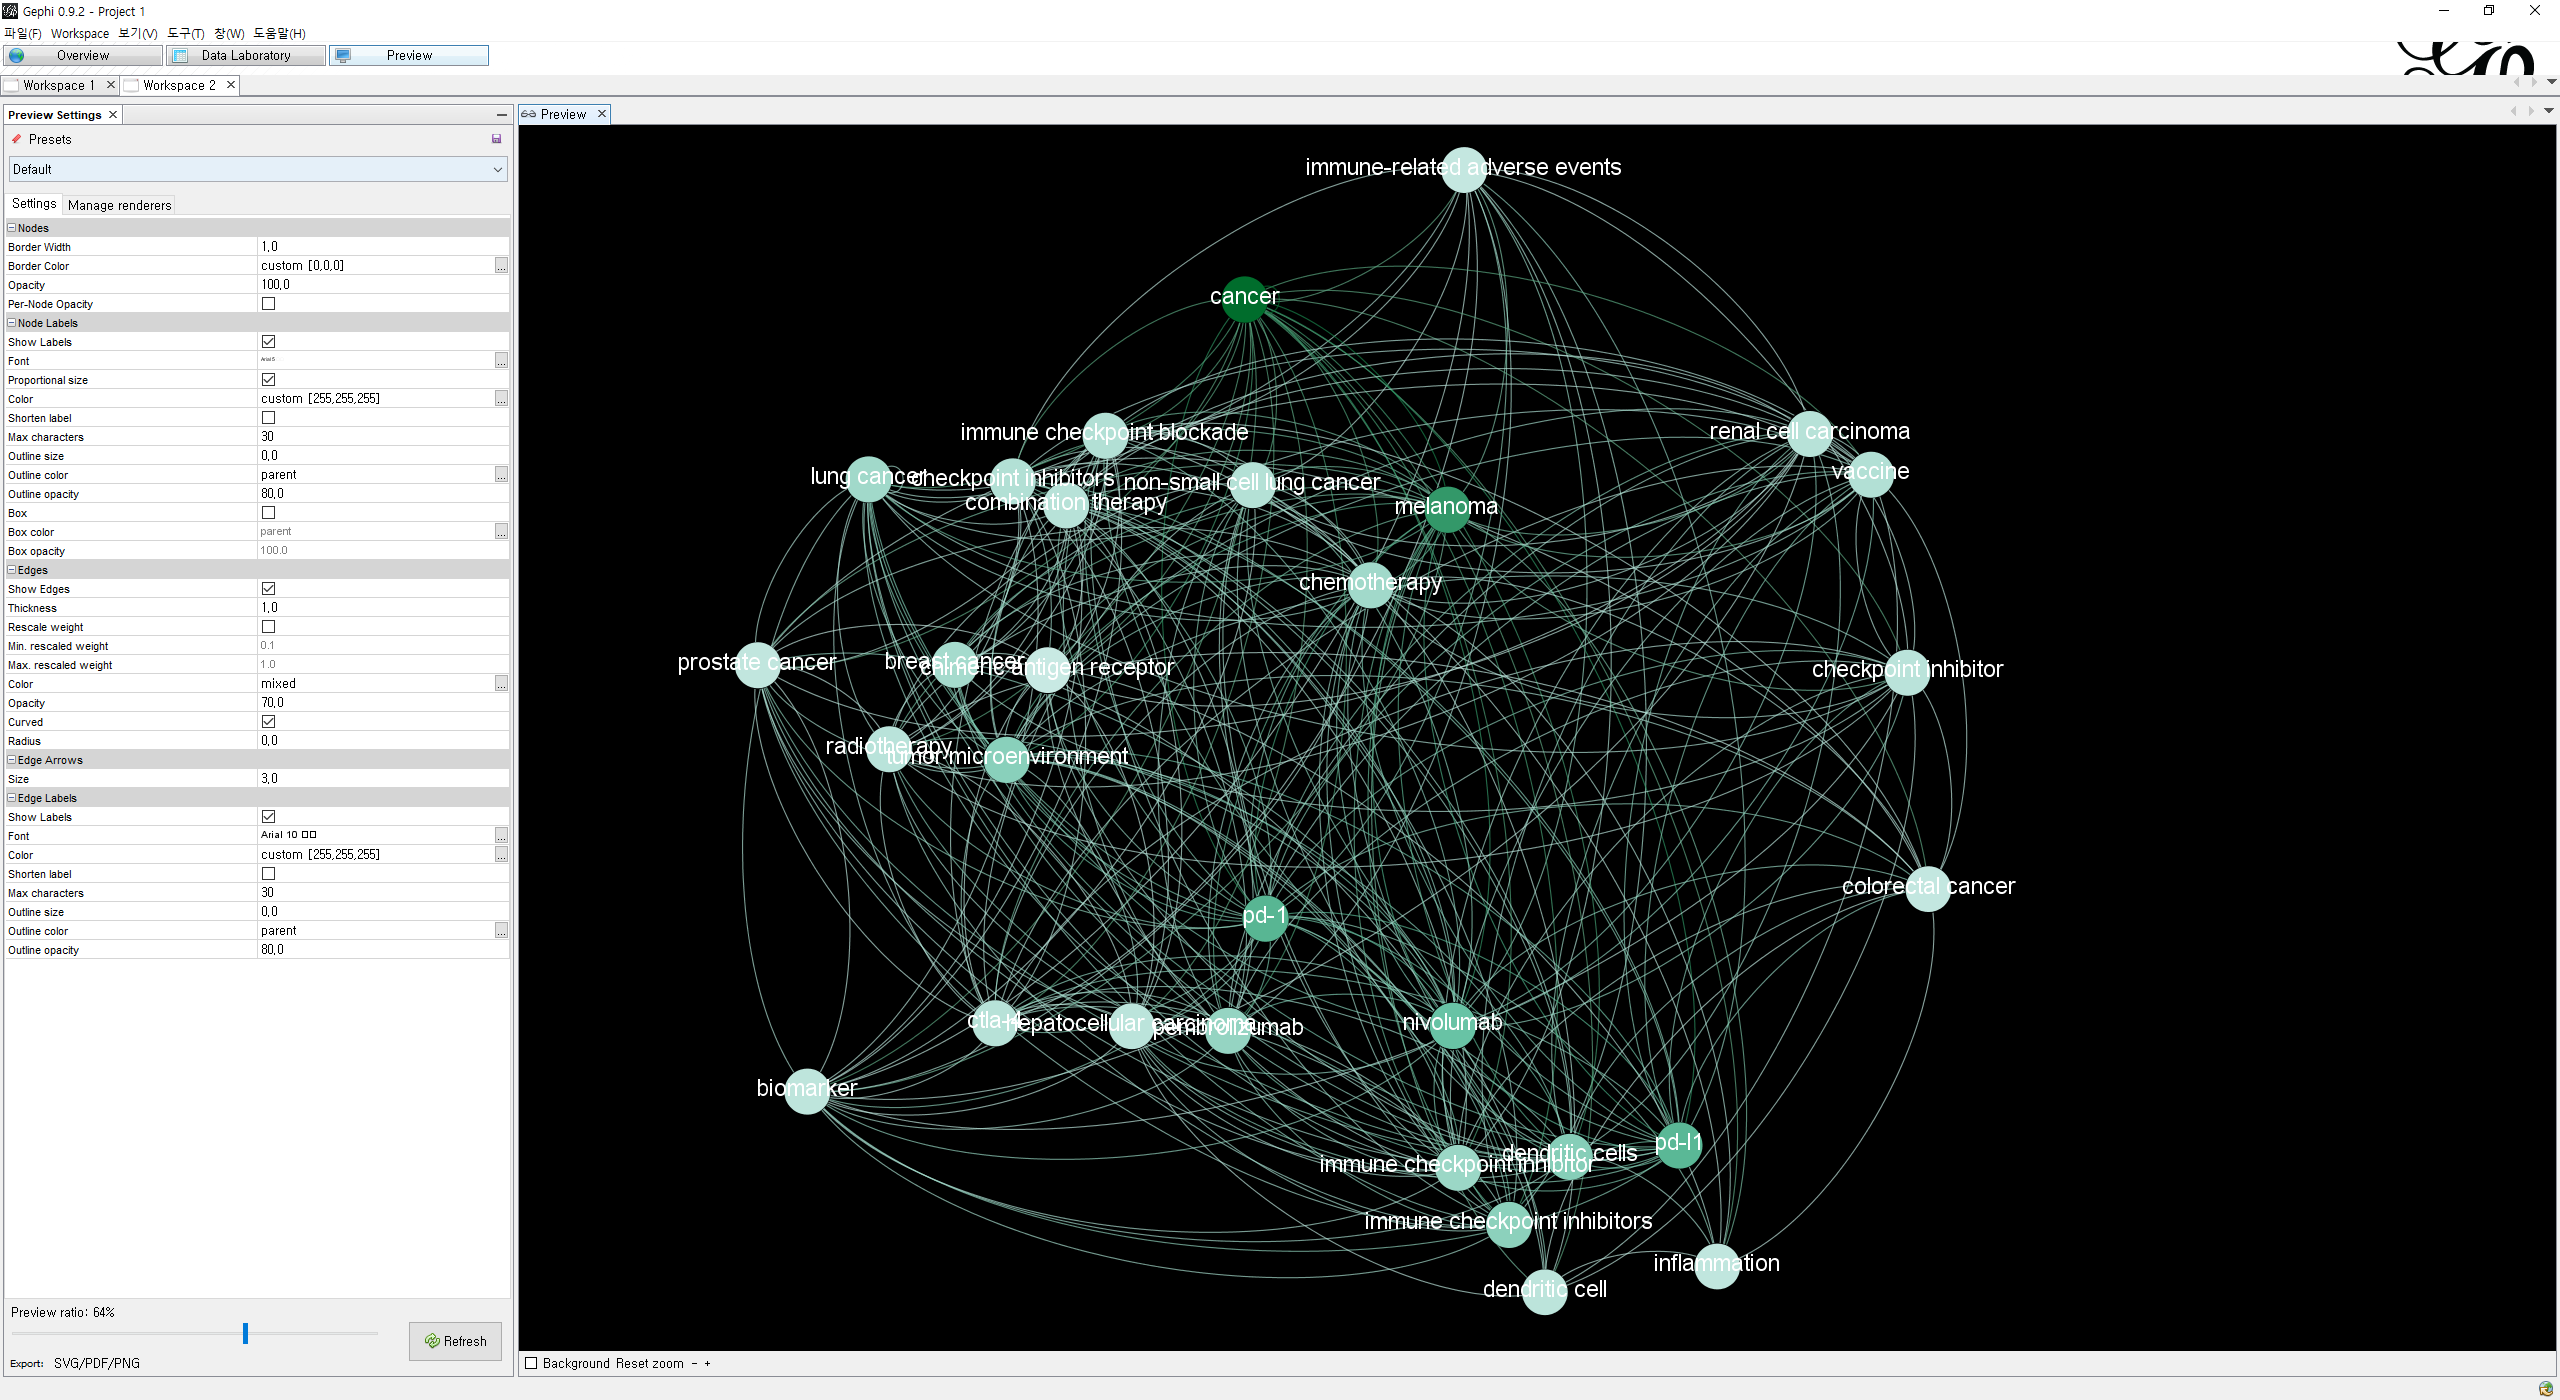

데이터 셋을 불러서 노드들과 엣지들이 생성됐다면 레이아웃(위 사진의 왼쪽 아래)을 설정한다. 여러 레이아웃이 있지만 나는 Force Atlas를 사용했다. 레이아웃을 적용하고 우측에 Statistics에서 여러 도구들 중 필요한 것을 선택(Run)한다. 기본적인 Degree, Betweenness을 사용하기 위해서는 Edge Overview의 하위 항목인 Avg. Path Length를 실행해야 한다.

실행하면 데이터 셋을 기반으로 분석한 결과를 리포팅 해 주며 왼쪽 상단의 영역에서 DC, BC, EC 등 중심성 계산하여 랭크, 파티셔닝 하는 것이 가능해 진다. 위 사진은 DC를 기준으로 랭크에 따른 노드의 색상을 변경한 것이다.

노드가 약 2만개 정도가 있었기 때문에 상위 노드들만 추출을 해야 시각화를 하는 것이 의미있다고 생각한다. 그래서 데이터를 필터링하였다. 위는 Edge의 개수가 190개 이상인 것들만 필터링하고 라벨링을 하여 노드들의 이름을 지어준 것이다.

이제 데이터 순위화, 필터링도 했으니 상단의 Preview를 클릭해 만들어진 그래프를 자기 입맛에 맞게 바꿔야 될 시간이다. 나는 배경색을 검은색, 글자색은 하얀색으로 하여 몽환적인 느낌으로 그래프를 만들어 보았다. 이후에 만들어진 그래프는 PNG, SVG로 Export할 수 있다.